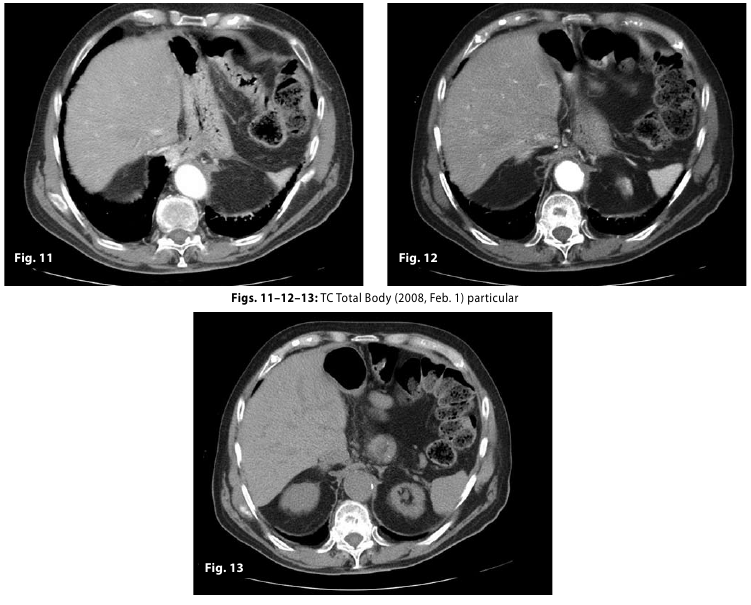

Figure11-12-13